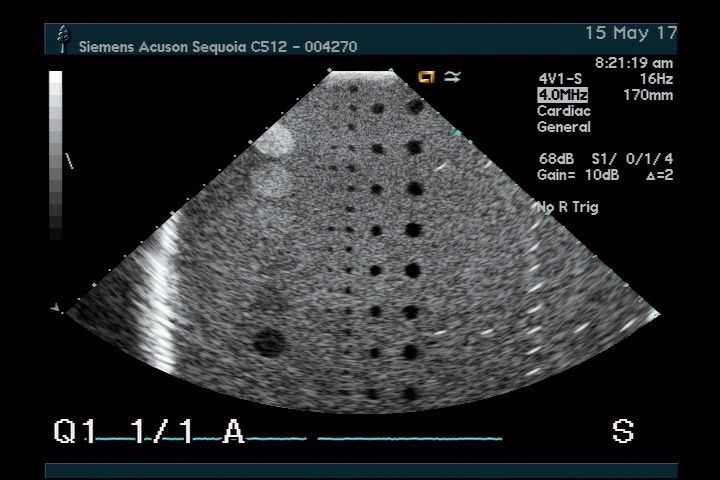

The Acuson 4V1 for Sequoia Ultrasound Transducer offers exceptional imaging capabilities. It provides clear, detailed images that are crucial for accurate diagnostics. Because of its advanced technology, this transducer is able to produce high-resolution images, so healthcare professionals can easily identify and assess various medical conditions. Furthermore, the ergonomic design of the Acuson 4V1 ensures comfort for both the patient and the clinician during examinations.

This transducer is not just limited to one type of examination; it is highly versatile and can be used for various applications in different clinical settings. Whether it’s for cardiac imaging, abdominal assessments, or vascular studies, the Acuson 4V1 meets the diverse needs of healthcare providers. Because it covers a wide range of frequencies, it allows for tailored imaging techniques, enhancing diagnostic accuracy. Thus, it becomes an essential tool in any medical facility.